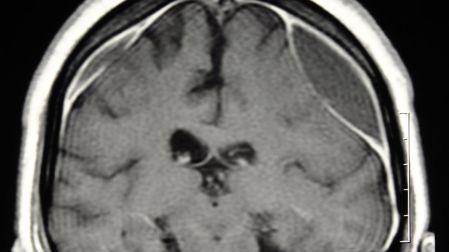

Un hematoma subdural es una acumulación de sangre entre el cerebro y su capa protectora más externa, llamada duramadre. Este sangrado ocurre cuando se rompen pequeños vasos sanguíneos, por lo general después de un golpe en la cabeza.

De acuerdo con Mayo Clinic, esta acumulación de sangre provoca presión dentro del cráneo. Como el cerebro no tiene espacio para expandirse, esa presión puede afectar funciones esenciales como la memoria, el movimiento o la conciencia.

El National Institutes of Health (NIH) advierte que, en casos graves, el aumento de presión puede desplazar el cerebro, una complicación que pone en riesgo la vida.